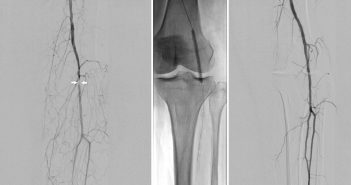

Seit etwa einem halben Jahr kann das Uniklinikum Würzburg Patienten mit extrem verkalkten, verengten peripheren…